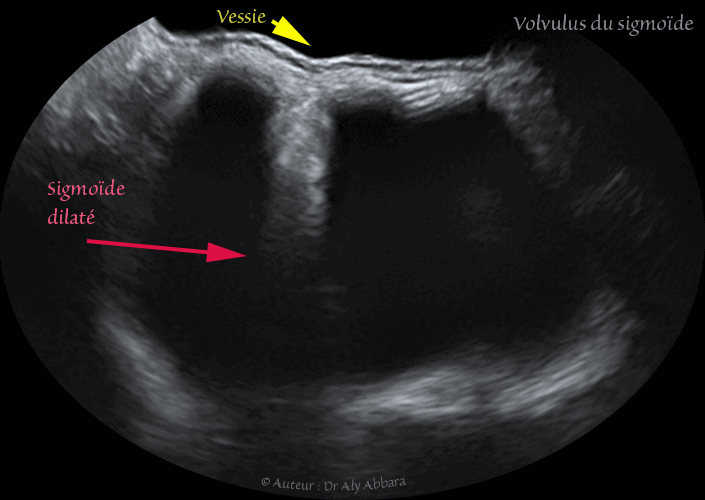

Volvulus du sigmoïde - Aspect échographique - انفتال القولون السيني - المظهر التصويري الصدوي

Images échographiques animées montrant l'aspect ultrasonique et d'un volvulus du sigmoïde chez une patiente âgée de 21 ans.

I- fomation kystique rétrovésicale haute, avec un repli de la paroi antérieure vers la cavité kystique.

II- cette formation mesure 94 x 61 x 60 de grands axe, mais il s'agit d'une masse changeant de forme et de taille continuellement, surtout au cours l'accentuation de la douleur (douleur intensse, de type colique).

III- Le contenu de cette formation kystique est hypo-échogène (suc digestif) avec la présenec des amas flottant correspondant aux matières fécales.